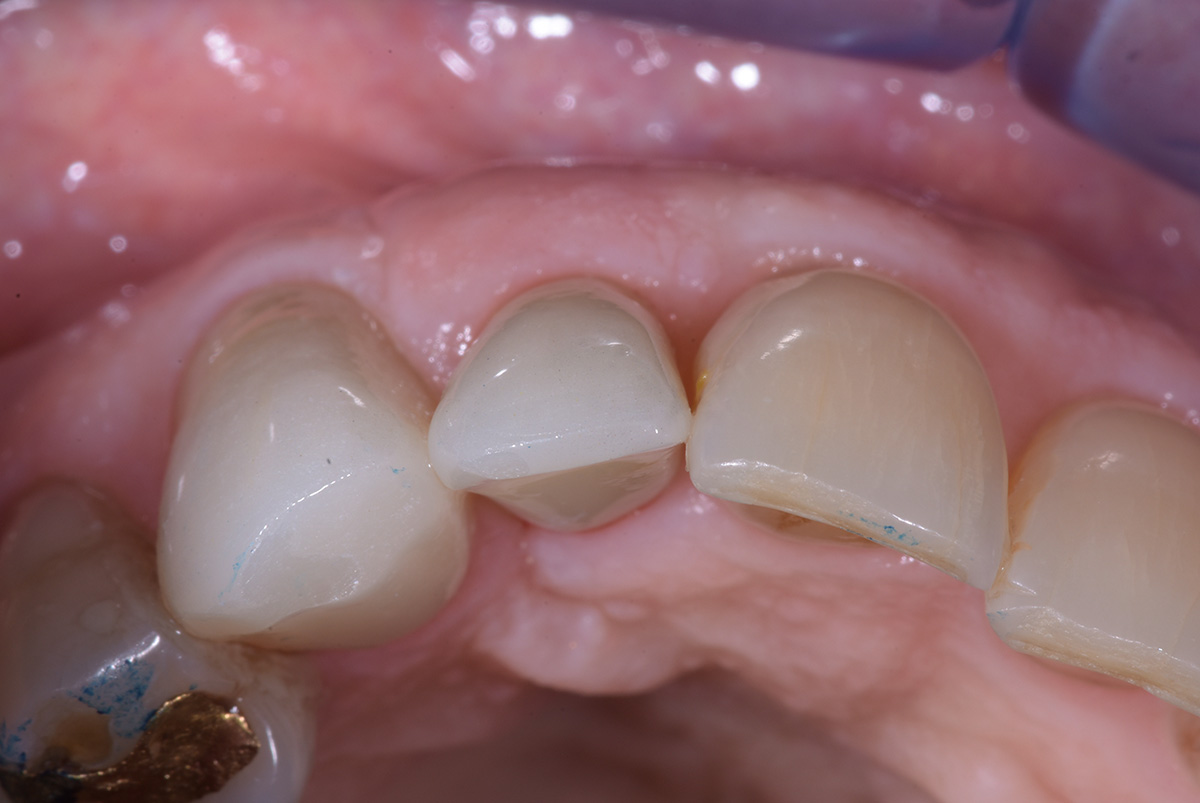

Correzione estetica mucogengivale, mediante innesto di connettivo, di esposizione impianto di incisivo laterale sup dx, con rifacimento protesico di laterale e canino.